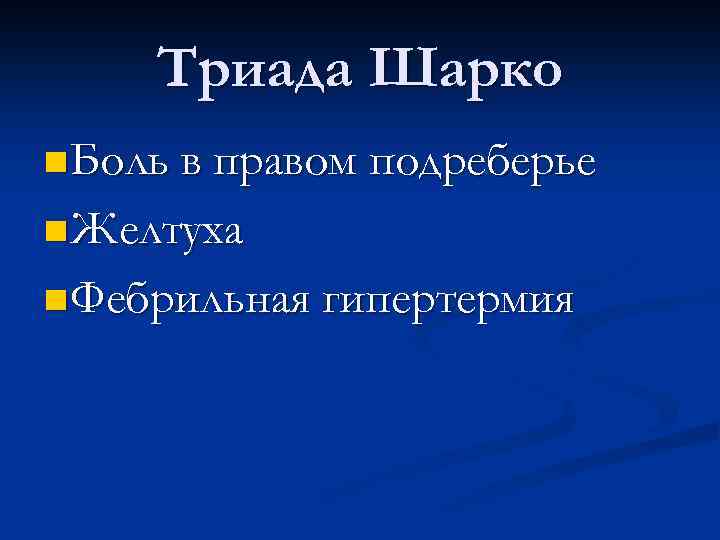

Триада Шарко n Боль в правом подреберье n Желтуха n Фебрильная гипертермия

Триада Шарко n Боль в правом подреберье n Желтуха n Фебрильная гипертермия